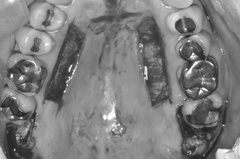

上顎写真

上顎写真